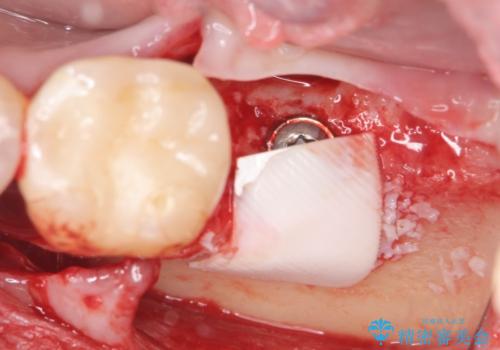

歯の抜去を行い、骨の造成を含めたインプラントによる咬合機能の回復を図ります。

- 44万円(インプラント・チタンカスタムアバットメント・ジルコニアクラウン・仮歯)費用は治療当時の料金となります